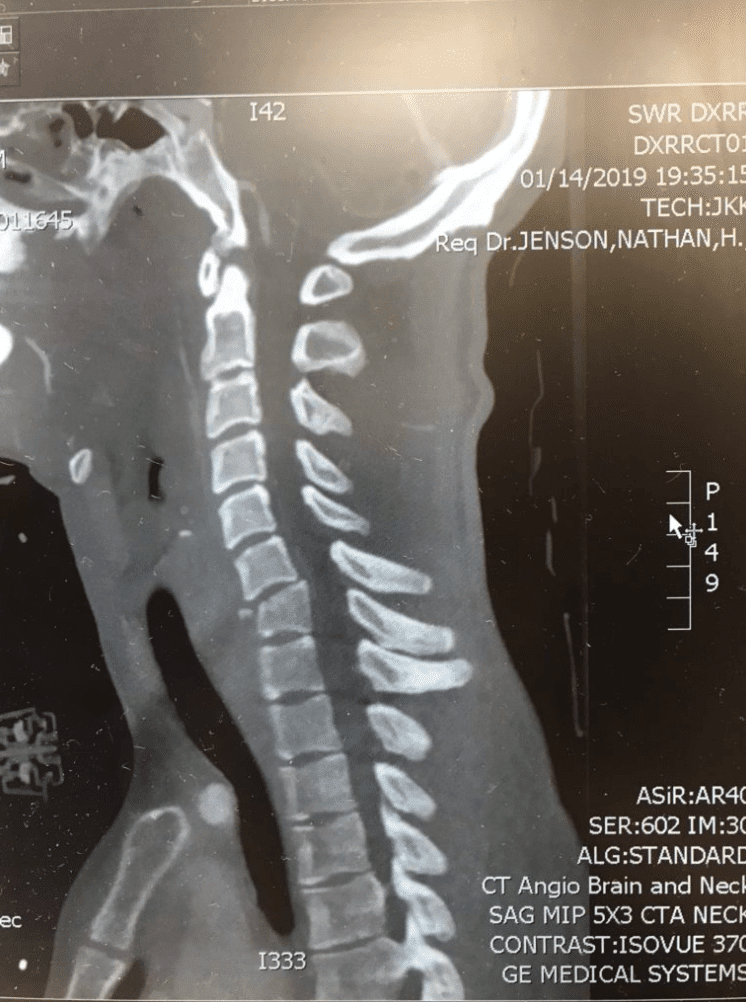

Earlier this month on January 14, 2019, Blake Savage crashed while riding at a private supercross track in Mesquite, Nevada, sustaining a cervical spinal cord injury due to fractures to his C6 and C7 vertebra. Savage was immediately transported to Dixie Regional Medical Center in St. George, Utah, where his injuries were assessed and a surgical plan was quickly put into place. On Tuesday, January 15, Savage underwent successful surgery, where doctors completed a C5 to T1 posterior spinal instrumentation and fusion, which addressed the fractures and stabilized the spine.